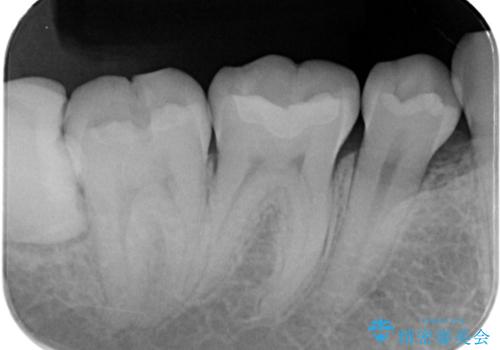

- 銀歯を外したいことを主訴に来院されました。

銀歯を丁寧に取り除き、形態を整えた上で、セラミックインレーで修復しました。

当院のセラミックインレーはe-max プレスインレーで製作しています。